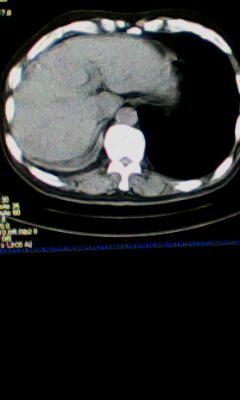

标题: CT25675:男 71 肺癌部分切除术后 3年 [打印本页]

标题: CT25675:男 71 肺癌部分切除术后 3年

1)两肺感染性病变。2)右侧胸膜增厚。3)冠状动脉及主动脉钙化。

右肺癌切除术后。

1.右肺符合肿瘤切除术后ct表现。

术后改变,双肺内纤维索条影考虑与放疗有关。